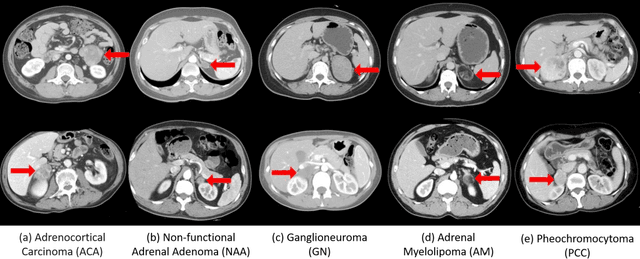

Abstract:Objective: The accurate classification of mass lesions in the adrenal glands ('adrenal masses'), detected with computed tomography (CT), is important for diagnosis and patient management. Adrenal masses can be benign or malignant and the benign masses have varying prevalence. Classification methods based on convolutional neural networks (CNN) are the state-of-the-art in maximizing inter-class differences in large medical imaging training datasets. The application of CNNs, to adrenal masses is challenging due to large intra-class variations, large inter-class similarities and imbalanced training data due to the size of masses. Methods: We developed a deep multi-scale resemblance network (DMRN) to overcome these limitations and leveraged paired CNNs to evaluate the intra-class similarities. We used multi-scale feature embedding to improve the inter-class separability by iteratively combining complementary information produced at different scales of the input to create structured feature descriptors. We also augmented the training data with randomly sampled paired adrenal masses to reduce the influence of imbalanced training data. We used 229 CT scans of patients with adrenal masses. Results: Our method had the best results compared to state-of-the-art methods. Conclusion: Our DMRN sub-classified adrenal masses on CT and was superior to state-of-the-art approaches.